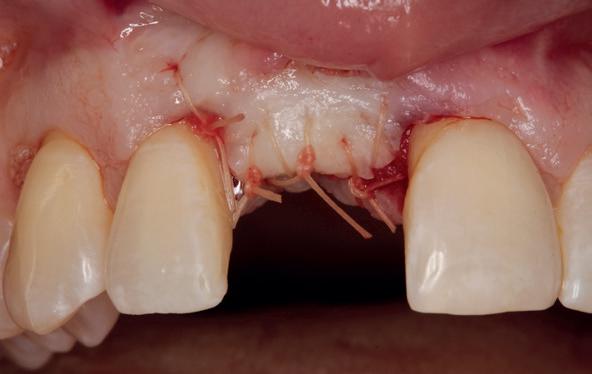

Lateraal van de implantaten wordt de kaak fors uitgebouwd volgens de Hybride GBR-techniek met Oragraft (allograft) van Lifenet die wordt vermengd tot een cocktail met BioOss (xenograft) van Geistlich, autoloog geoogste botsnippers en verzameld bloed uit het wondgebied. De botgraft wordt bedekt met een Ossix (crossed linked) membraan en met Hyadent (hyaluronzuur) overspoten. De sinuslift wordt gelijktijdig met de laterale botopbouw volgens de Caldwell Luc methode uitgevoerd en de uitgeprepareerde holte opgevuld met de botgraft. De flaps worden eerst horizontaal ontlast (gemobiliseerd) en vervolgens naar elkaar toe gehecht met vicryl rapide. Daarbij wordt gebruikgemaakt van horizontale matrassen, zodat de wondranden passief tegen elkaar

komen te liggen en de flaps primair gesloten kunnen worden. Het passief sluiten van een flap voorkomt wonddehiscenties in de genezingsfase die als complicaties kunnen optreden en botregeneratie verstoren. Daarnaast wordt bij een wonddehiscentie het risico op infectie van de graft sterk verhoogd waardoor het gewenste resultaat niet kan worden bereikt. Afstoting van graft materiaal komt dan veelvuldig voor soms gecombineerd met abcesvorming als geen voorzorgsmaatregelen worden genomen. Complicaties moeten daarom nauwlettend gevolgd worden totdat ze verdwenen zijn. De patiënt krijgt na chirurgie postoperatieve instructies en adviezen over de postoperatieve zorg. Daarbij wordt ook de nadruk gelegd op het koelen (coldpack) en zijdelingse druk op de wang. Het blijkt dat koelen en het uitoefenen van druk op het operatiegebied oedeem en hematoomvorming grotendeels kunnen verminderen en soms zelfs kunnen voorkomen.